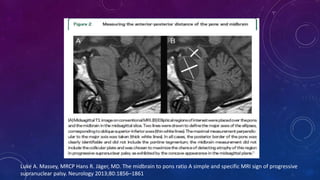

Luke A. Massey, MRCP Hans R. Jäger, MD. The midbrain to pons ratio A simple and specific MRI sign of progressive

supranuclear palsy. Neurology 2013;80:1856–1861